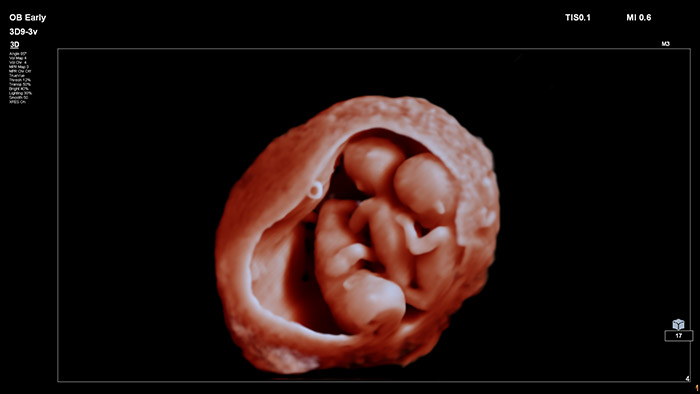

En este vídeo, el Dr. Michael Ruma presenta el transductor V9-2 para ultrasonidos 3D de Philips. El V9-2 es el primer transductor mecánico PureWave para ultrasonidos 3D de la división de ultrasonidos de Philips específico para obstetricia/ginecología y ofrece una extraordinaria calidad de imagen y un diseño ergonómico avanzado. El V9-2 está especialmente indicado para la adquisición de imágenes 2D, 3D y 4D para exploraciones obstétricas del primer, segundo y tercer trimestre..

Combinar el nuevo transductor V9-2 con el sistema de ultrasonidos de alta gama EPIQ Elite ofrece una adquisición de imágenes superior de obstetricia/ginecología: